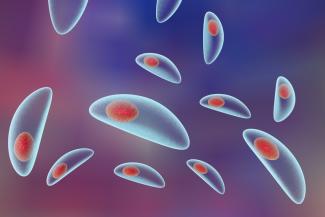

- Toxoplasmosis bir protozoon olan toxoplazma gondii tarafından oluşturulan hücre içi paraziter bir enfeksiyondur...